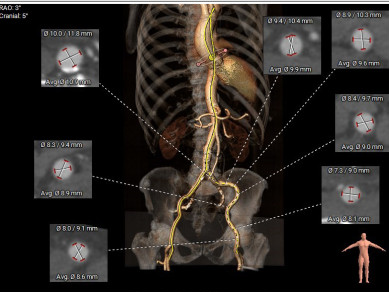

患者术前CT分析:患者主动脉瓣为三叶式,瓣叶重度钙化伴增厚;左侧冠脉开口9.1mm稍低;主动脉弓角度偏小。

外周血管通道